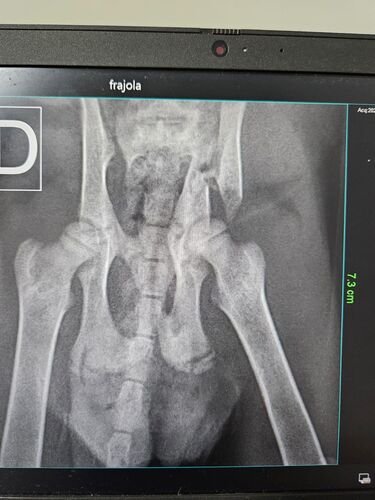

Após resgatada foi levada a clínica veterinária e após ser feito RX constatou-se a fratura, ela precisa fazer :